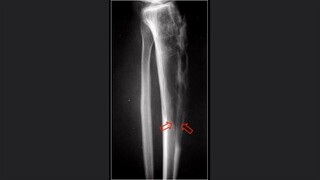

Generalidades de la fractura

La osteoradiología

Miembros Inferiores